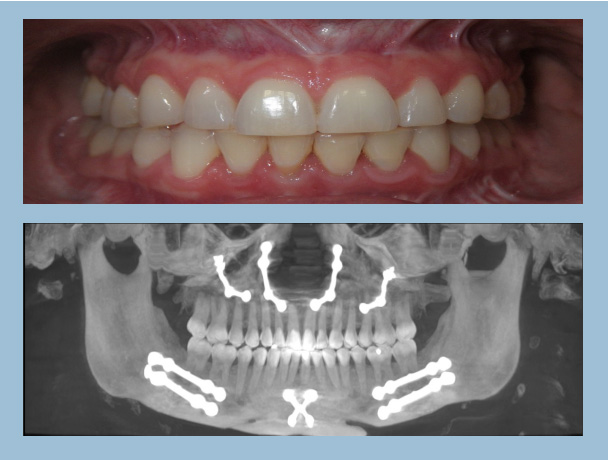

Figure 1. Photos courtesy of Dr. JB’s periodontist

• Nasal and jaw surgery with minimal improvement in her sleep and jaw pain— see the hardware in Figure 9

Figure 9: Straight white teeth in a miserable physician owner